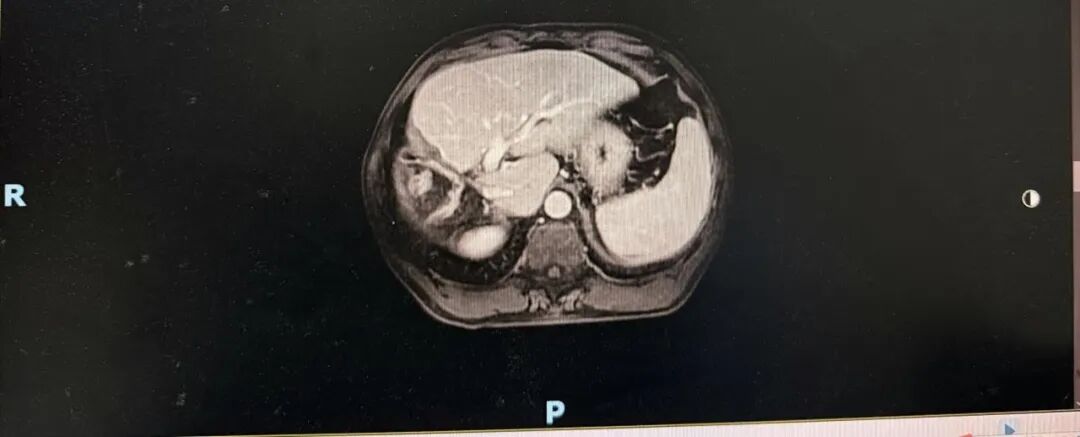

➣ 2021-04-9,MRI:术区未见确切肿瘤复发征象。

➣ 2021-11-24,MRI:术区未见确切肿瘤复发征象。

➣ 2021-04-8,CT:肝右叶、胆囊未见显示,考虑术后改变,术区未见确切肿瘤复发征象。

➣ 2021-11-23,CT:肝右叶、胆囊未见显示,考虑术后改变,术区未见确切肿瘤复发征象。